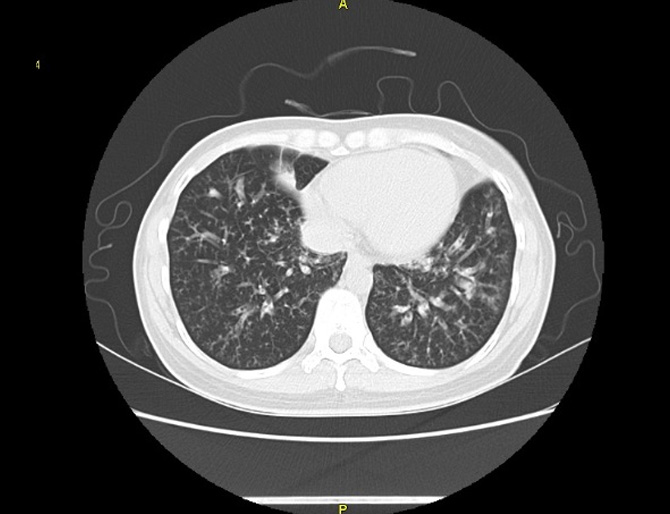

비결핵항산균에 감염된 폐사진